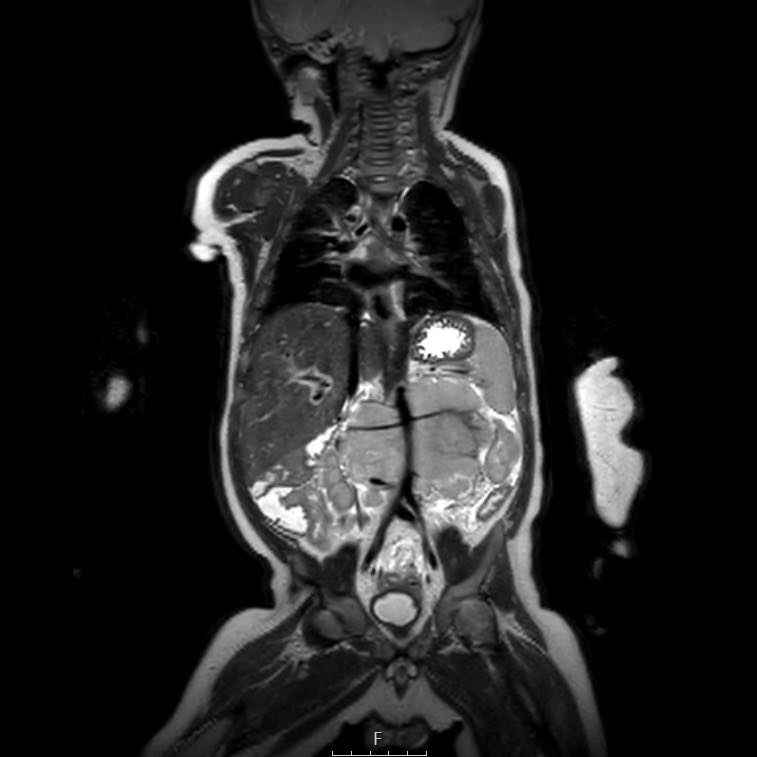

Mức độ lan rộng của khối u được đánh giá rõ ràng trên chuỗi xung TSE T2 weighted 3D theo mặt phẳng axial.

The left kidney is compressed and displaced caudally.

Có di căn hạch bạch huyết cạnh động mạch chủ (mũi tên vàng nhỏ).

Nguyên ủy của thân tạng và động mạch mạc treo tràng trên bị khối u bao quanh (đầu mũi tên).

Tĩnh mạch chủ dưới bị đẩy ra phía trước (mũi tên xanh).

Xẹp phổi hai bên ở vùng lưng thường được thấy trên MRI, vì việc kiểm tra được thực hiện dưới gây mê.

Ví dụ 1

Một bé gái ba tuổi có khối u thận trái và huyết khối khối u lớn trong tĩnh mạch thận và tĩnh mạch chủ dưới. Có di căn gan (phát hiện không thường gặp) và di căn phổi.

Lưu ý huyết khối u trong tĩnh mạch thận trái kéo dài vào tĩnh mạch chủ dưới.